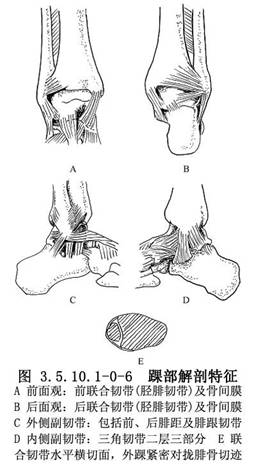

踝關節由脛腓骨下端與距骨體上面組成,內外踝及副韌帶維持其穩定(圖3.5.10.1-0-1~3.5.10.1-0-3)。

側副韌帶控制距骨滾動。內側三角形副韌帶較強,有二層三部分,限制足外翻。外踝較長,內側韌帶又強,故足外翻動作小。反之,內踝短,外側韌帶弱,內翻動度較大,故外側韌帶損傷較多發(圖3.5.10.1-0-4,3.5.10.1-0-5)。

距骨前面較寬,當距骨在背屈弧度上活動時,距骨與踝穴緊密接觸,踝有輕度旋轉動作。而當跟骨觸地時,外踝及其韌帶複合體所受剪力幾等於1/4關節壓力。

下脛腓韌帶連結維持緊張的踝穴,在踝關節水平有較弱的前聯合韌帶連接脛骨前結節與外踝。強的後聯合韌帶則在外踝與脛骨間形成三角形。脛腓關節近側則爲骨間膜。

踝穴的完整主要依靠腓骨的正確長度及其在脛骨的腓骨切跡的實際位置,與完整的脛腓韌帶,此包括前後韌帶及骨間膜(圖3.5.10.1-0-6)。